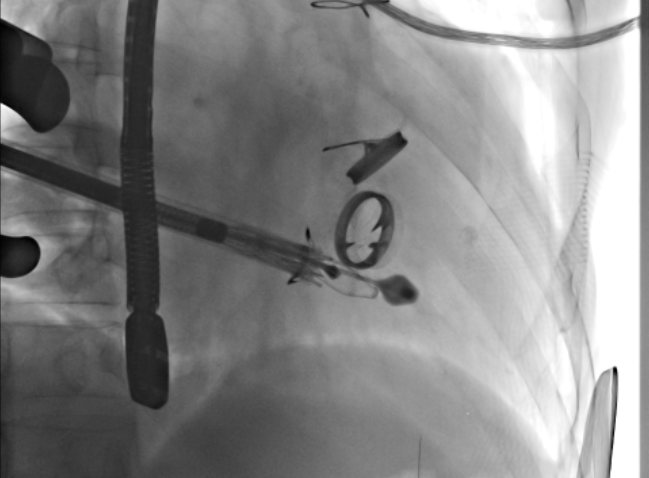

根据术前CT的测量结果,选择使用JS/TTVI-28-40型号的LuX-Valve®瓣膜。陆方林教授用导管顺利将介入瓣送入右心室,过三尖瓣瓣环到达右心室,精准地控制着输送系统,最终和超声确认无瓣周漏后对瓣膜进行锚定,术后超声和造影显示瓣膜位置良好,几乎无反流。

瓣膜释放过程中

瓣膜植入术后右心室造影